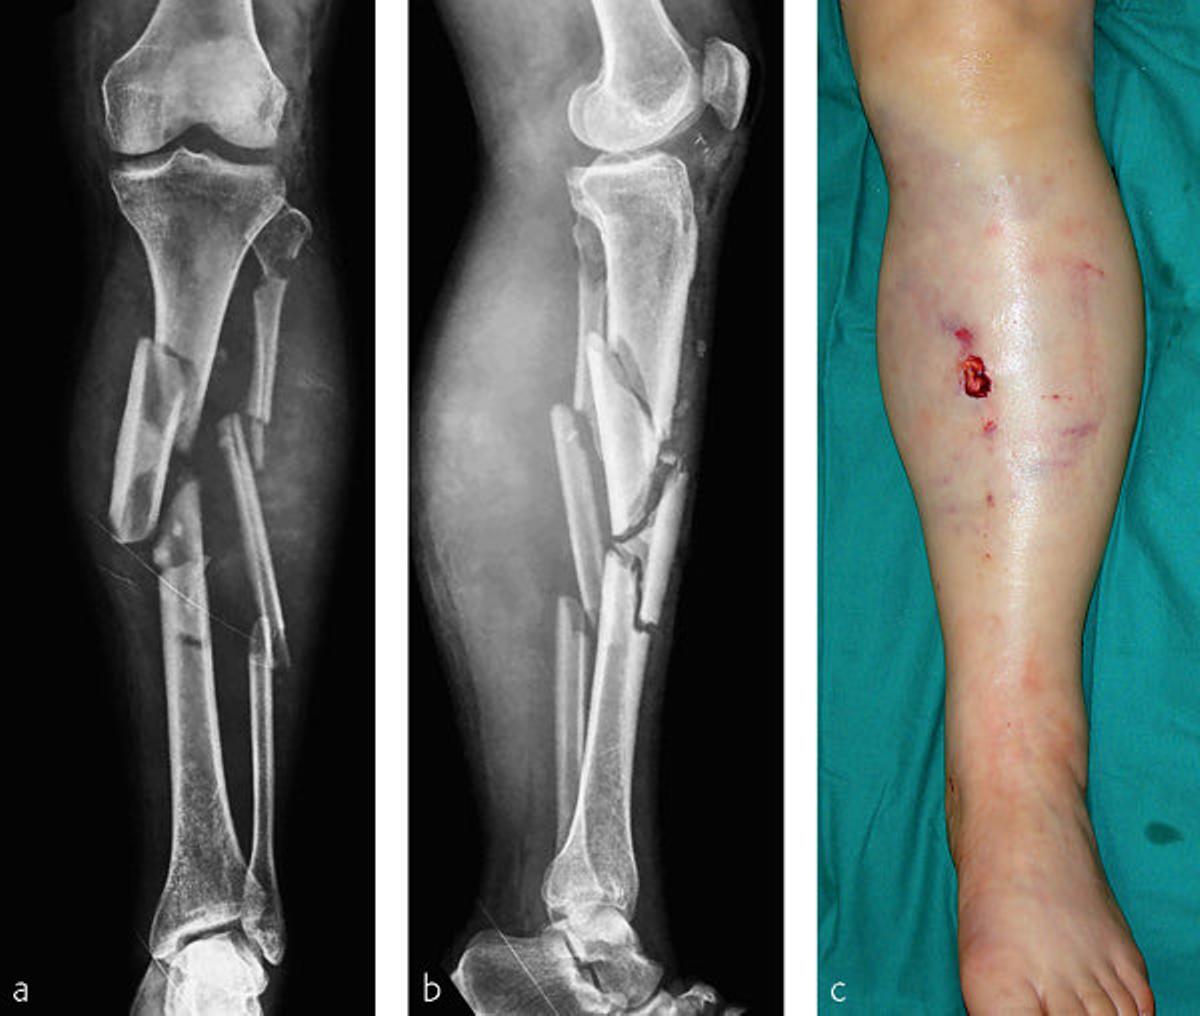

"Cuando digo que fue una fractura 'terrible' no estaba bromeando. Esto se llama fijador externo ('x-fix') y se utiliza para ayudar a estabilizar la tibia fracturada (y quizás más)", añade el especialista, que también aporta una imagen (de otro paciente) para reflejar la situación que atraviesa Lindsey Vonn. "Mucha suerte para ella", le desea.

Imagen que explica la situación que atraviesa Lindsey Vonn / RRSS